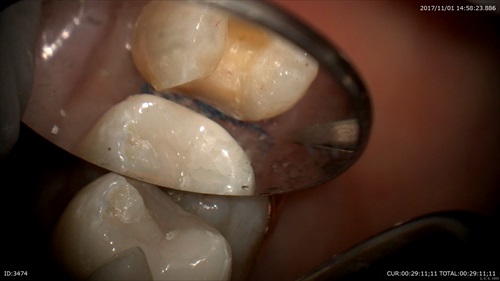

2ケース目

精密な型取り:インレー(はめこむ治療)の際にも歯と歯茎の境をしっかりだします。

型取りの材料をいれる直前

良くみえますね。

このように精密な型を採ることにより歯と詰め物の隙間をなくし2次感染をふせぎます。